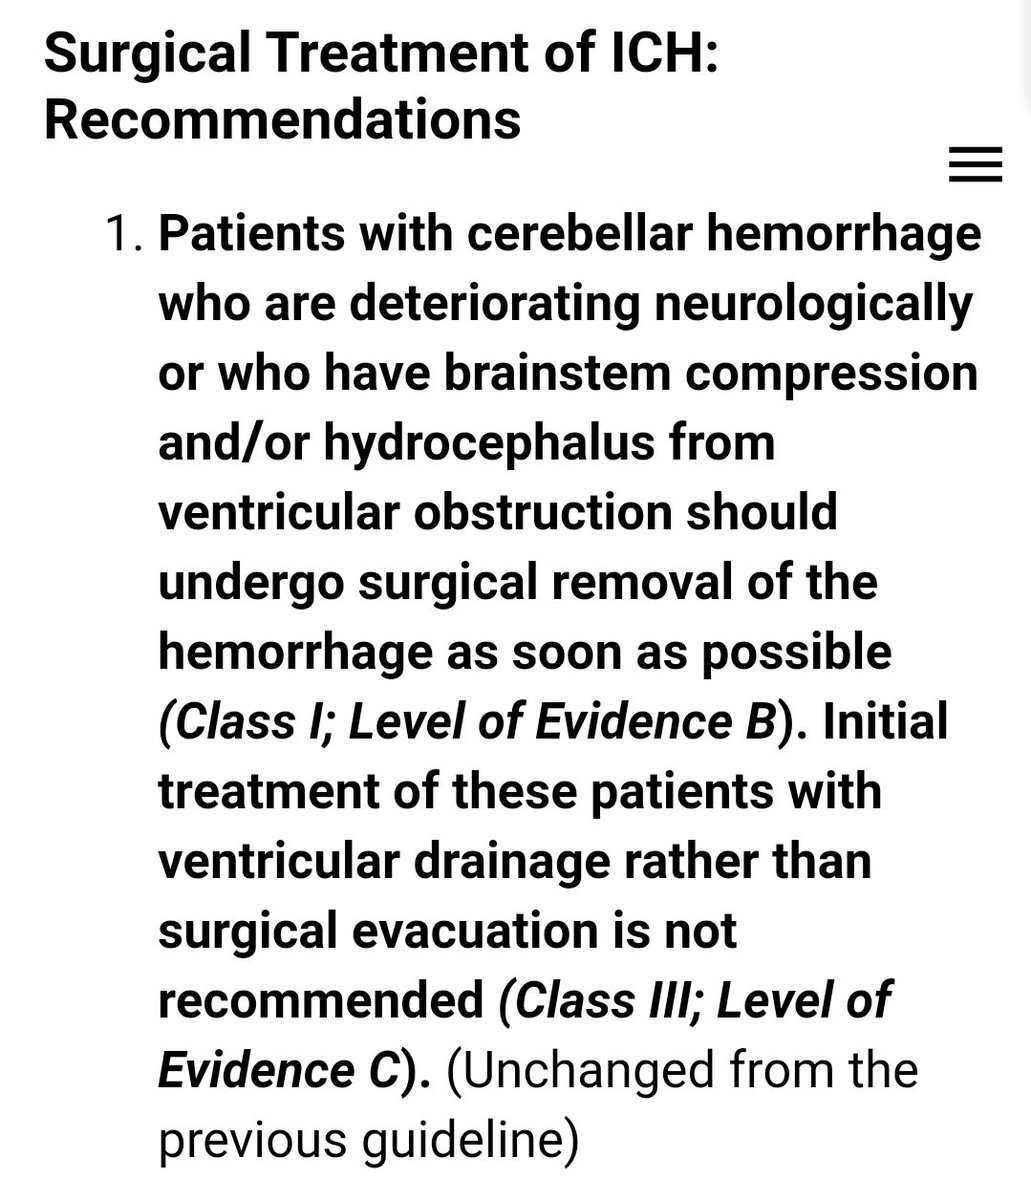

#السكته_الدماغيه_النزفيه

للاطباء🧠

Guidelines for the Management of Spontaneous Intracerebral Hemorrhage

للاطباء🧠

Guidelines for the Management of Spontaneous Intracerebral Hemorrhage